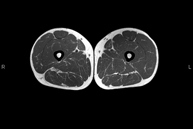

- Thigh MRI

Ideal examination for studying injuries to the hamstrings and quadriceps, which are frequently injured in athletes. It also allows for a good assessment of tendons and peripheral nerves. It lasts approximately 20 minutes. It is a radiation-free procedure.